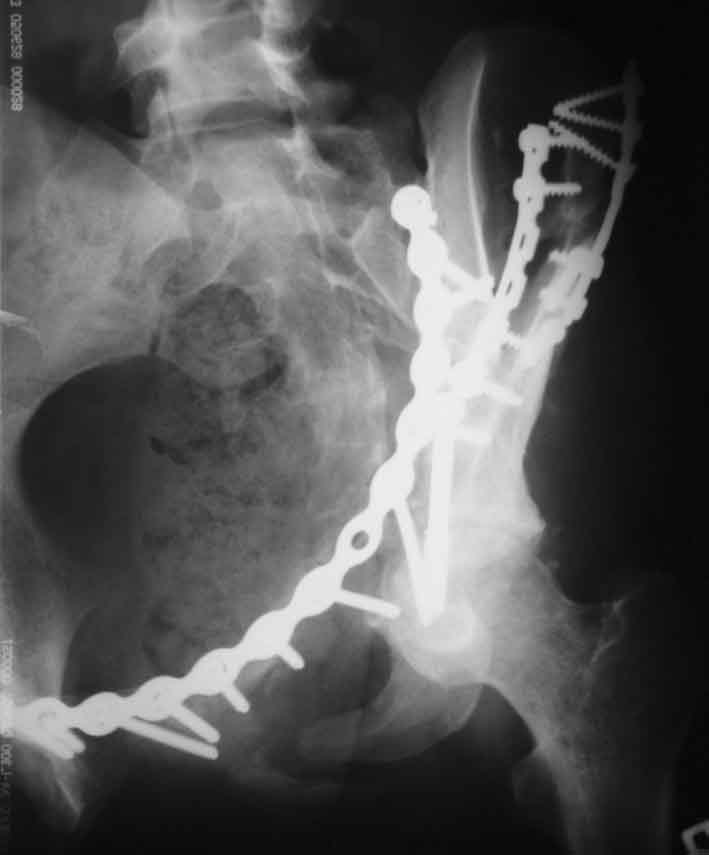

Рентгенограмма после операции. Изв. за качество. На днях переделаем.

Рентгенограммы после операции

Прямая проекция

inlet

подвздошная

запирательная

A>РО - картина не очень, есть видимость винтов во впадине

По всей видимости, вы имеете в виду канюлированный винт, который проецируется на вертлужной впадине. Та вот, он проведен не через лонную, а седалищную кость. Вертлужная впадина абсолютно интактна. Это хорошо видно на проекции inlet.